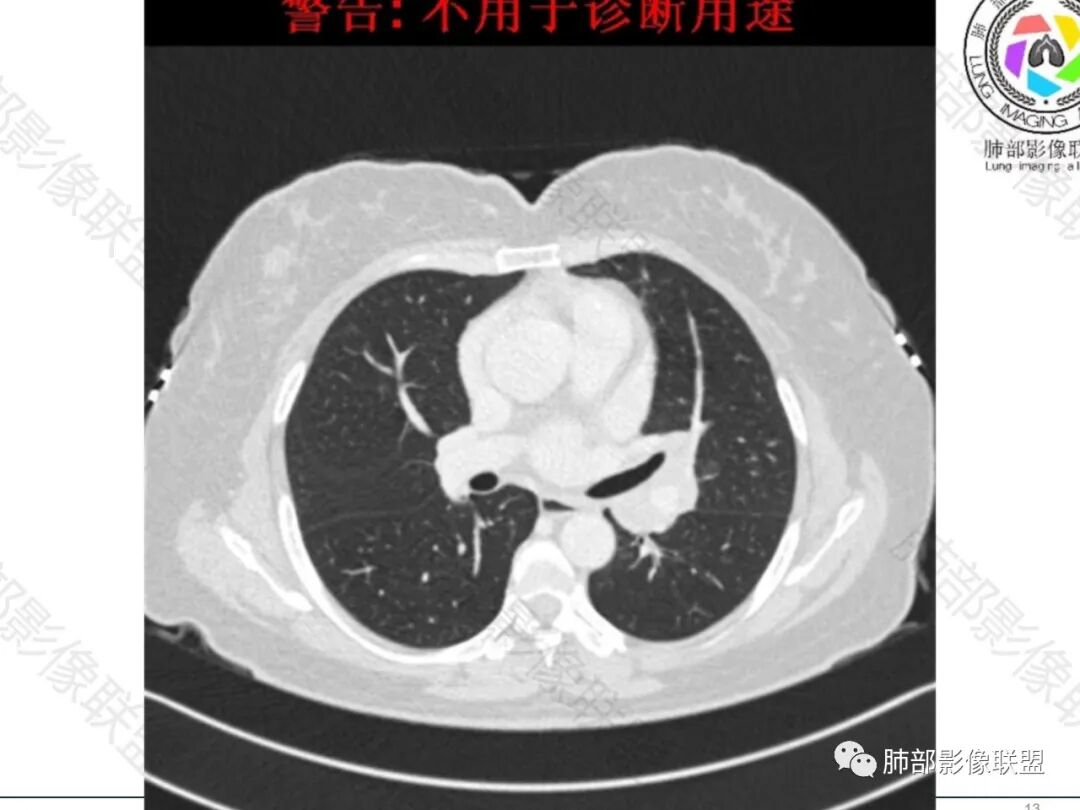

中年女性患者。左肺门上区, 围绕左肺动脉及支气管旁不规则形的病灶,支气管无变窄,肿块塑形增长,密度均匀,增强后边界比较清楚,肿块未见强化。临床提供给的病史价值不高,表现为轻咳,偶感乏力。影像学表现出偏温和的特点。考虑淋巴瘤。

左侧多组(10.11.12)淋巴结肿大融合,无明显坏死,增强轻中度强化,肺内无明显病灶。纵隔内见淋巴结肿大(影像上恶性意义不大)。常规恶性可能,转移,淋巴瘤。良性(结核,结节病)这样表现少见。

左肺门淋巴结肿大,纵隔淋巴结未见明显肿大,均匀强化,血管包埋漂浮,考虑:淋巴瘤和小细胞癌鉴别,单侧结节病少见

中年女性,慢性病程,轻咳,乏力。实验室检查无。影像见左肺门多发淋巴结肿大,部分融合,轻度均匀强化,血管包埋漂浮,主要疾病谱:淋巴瘤、小细胞肺癌、结核、转移、结节病。

左肺门淋巴结肿大,支气管呈针孔样狭窄,均匀强化,血管包埋漂浮,考虑小细胞癌,鉴别淋巴瘤。

中年女性,左肺门多发淋巴结肿大,包绕血管,增强轻度强化,尚均匀,支气管未见明显变窄,考虑小细胞,鉴别淋巴瘤,转移瘤

左肺门为主,纵隔有一些,多发,融合成团,密度均匀,强化均匀,边界比较清楚

血管包绕其中,明显侵犯不典型

常规:转移瘤、淋巴瘤、结核